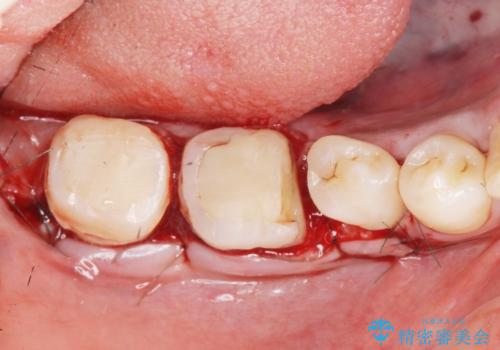

歯冠長延長術・骨隆起除去を行った、スペースの少ないセラミック治療

治療途中で長期間放置していたため、歯が歯ぐきから挺出(伸びてくる)してしまい、十分に強度を担保できるセラミッククラウンを装着するスペースが不足した状態です。

加えて、舌の邪魔になっている骨隆起や根尖病変といった問題を歯周外科・精密根管治療を行い、しっかりとスペースを確保したのちセラミッククラウンを作製していきます。

- 37.4万円(ジルコニアクラウン×2・仮歯×2・歯周外科手術)費用は治療当時の料金となります